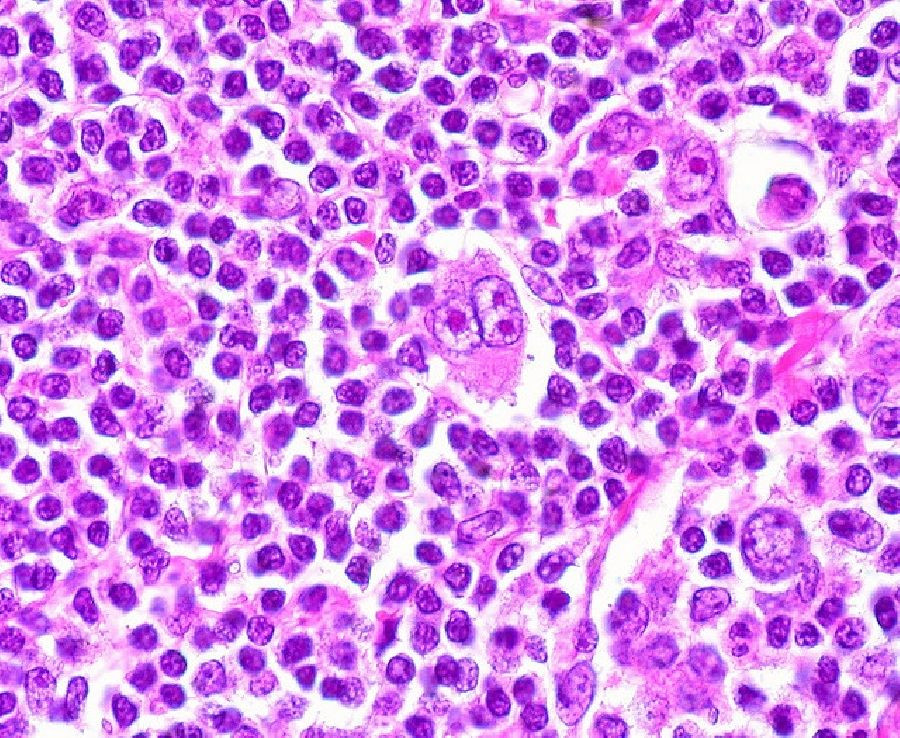

El linfoma no Hodgkin (LNH) es un grupo de cánceres que se originan en los ganglios linfáticos y afectan los glóbulos blancos del sistema inmunitario llamados células B, que crecen sin control y crean tumores en los ganglios linfáticos, el bazo u otros tejidos.

Un equipo de investigadores dirigido por Elisa Oricchio, investigadora de la EPFL, en Suiza, ha identificado uno de los mecanismos utilizados por el NHL para secuestrar el sistema inmune. Los científicos han descubierto que ciertos pacientes con LNH tienen una forma mutada y sobreactivada de una proteína llamada catepsina S, responsable de cortar otras proteínas en pequeños fragmentos que luego se exponen en la superficie de las células tumorales. Estos fragmentos median las comunicaciones entre el cáncer y las células inmunes.